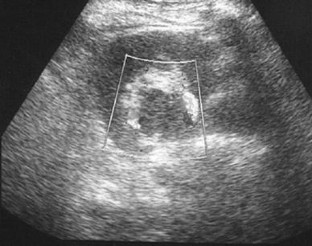

A 40-year-old woman was referred to our department for further investigation of a renal mass identified at an ultrasound (US) examination carried out in a private clinic because of abdominal pain. The mass was oval and hypoechoic, measured about 20 mm in diameter and was located near the left renal sinus; color Doppler showed peripheral blood flow. US examination carried out in our department using different equipment confirmed the presence of the mass but revealed intralesional blood flow suggesting aneurysm. This diagnosis was confirmed at subsequent computed tomography (CT) scanning and magnetic resonance imaging (MRI). The patient refused to undergo surgery and she is currently being monitored and has suffered no sequelae.

Fig. 2